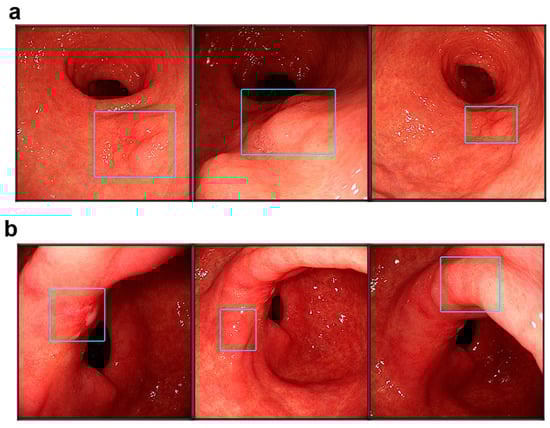

Open AccessArticle

Satoshi Osawa, Takanori Yamada, Wataru Inui, Tomoyuki Niwa, Kenichi Takahashi, Takatoshi Egami, Keisuke Inagaki, Tomohiro Takebe, Tatsuhiro Ito, Satoru Takahashi, Shunya Onoue, Yusuke Asai, Kiichi Sugiura, Tomoharu Matsuura, Natsuki Ishida, Mihoko Yamade, Moriya Iwaizumi, Yasushi Hamaya and Ken Sugimoto

Abstract

Background/Objectives: Artificial intelligence (AI)-assisted endoscopy has shown high sensitivity for early gastric cancer detection; however, false-positive diagnoses remain a clinical challenge. This study aimed to evaluate the real-world diagnostic performance of a commercially available AI system and to identify factors associated with false-positive diagnoses, focusing on repeated AI evaluations and confidence stratification. Methods: This single-center retrospective study included 47 patients with 89 localized gastric lesions evaluated between March 2024 and March 2025. Endoscopic examinations were performed under white-light, non-magnified observation with repeated AI assessments of each lesion. The rates of “Consider biopsy” (B) judgments were calculated. Lesions with a B judgment rate of ≥50% were defined as AI-positive and classified into four AI confidence categories. Diagnostic performance was assessed using sensitivity, specificity, positive predictive value (PPV), and negative predictive value (NPV). Factors associated with false-positive diagnoses were analyzed using penalized logistic regression. Results: The AI system demonstrated a sensitivity of 97.6% and an NPV of 95.7%, with a specificity of 45.8%. Pathology-positive rates decreased stepwise across the four AI confidence categories (p < 0.001). Among AI-positive lesions, low regional reproducibility, lesion size ≥ 30 mm, scar, and erosion were independently associated with false-positive diagnoses. In analyses restricted to non-neoplastic lesions, lesion size ≥ 30 mm remained significantly associated with false-positive diagnosis. Conclusions: In real-world clinical practice, a commercially available AI system provides high sensitivity for early gastric cancer detection. Incorporating confidence stratification and regional reproducibility into clinical decision-making may enhance the effective use of AI-assisted endoscopic diagnosis beyond binary interpretations.